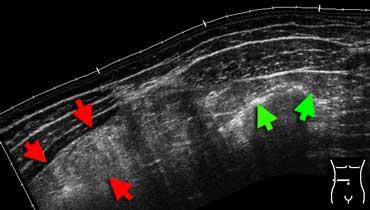

Mỡ viêm trên siêu âm. Hình ảnh toàn cảnh vùng bụng trước cho thấy một vùng mỡ mạc nối tăng âm, không đè xẹp được (mũi tên đỏ). So sánh với độ âm vang của mỡ bụng hoặc mỡ dưới da bình thường (mũi tên xanh). Bệnh nhân này được chẩn đoán nhồi máu mạc nối.

Mỡ viêm

Mỡ viêm có đặc điểm tăng âm, chiếm chỗ và không đè xẹp được trên siêu âm.

Cùng bệnh nhân trên. CT không tiêm thuốc cản quang cho thấy một vùng mô mỡ tăng tỷ trọng nhẹ (đầu mũi tên) ở góc phần tư trên phải. So sánh với mỡ dưới da bình thường có tỷ trọng thấp. Chẩn đoán: nhồi máu mạc nối.

Mỡ viêm biểu hiện dưới dạng dải mỡ (fat-stranding) trên CT. Mỡ viêm là dấu hiệu hữu ích giúp xác định vị trí và bản chất của tổn thương.

Theo nguyên tắc, cơ quan hoặc cấu trúc nằm ở trung tâm hoặc gần nhất với vùng mỡ viêm chính là nguyên nhân gây viêm.